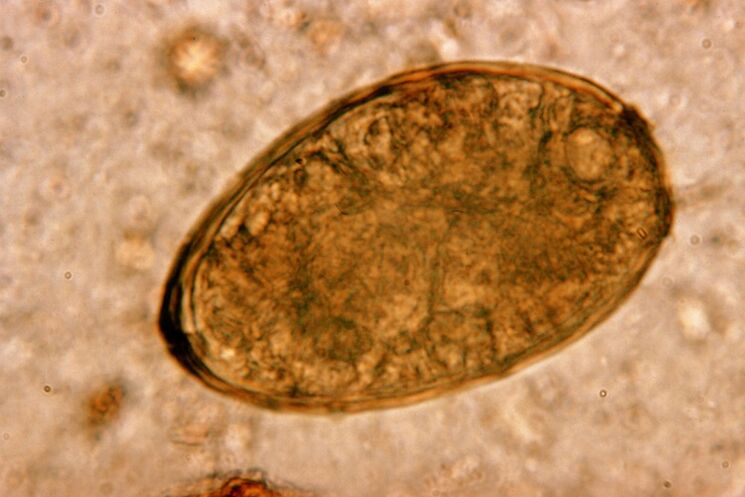

Lest elab kopsudes paarikaupa, moodustades bronhides tsüste. Nakatumine tekib parasiidiga nakatunud krabide ja vähkide söömisel. Seedetrakti sattudes tungib kopsulest läbi kõhukelme ja jõuab diafragma kaudu kopsudesse, põhjustades patsiendil püsivat köha.

Trematoodide klassi kuuluv väike helmintia kopsulest on "spetsialiseerunud" spetsiifiliselt kopsudes parasiteerimisele. See põhjustab hingamissüsteemis palju tõsisemaid probleeme kui näiteks ümarussid.

Selle lokaliseerimise kohas tekivad infiltraadid ja tekivad hemorraagiad, mille tagajärjel tekivad õõnsused, mis on täidetud usside, surnud parasiitide ja kopsukoe lagunevate metaboliitidega. Kopsutõve tekitatud kahju suurendab veelgi asjaolu, et tegemist on pika maksaga ja võib peremeesorganismis elada kuni 20 aastat.